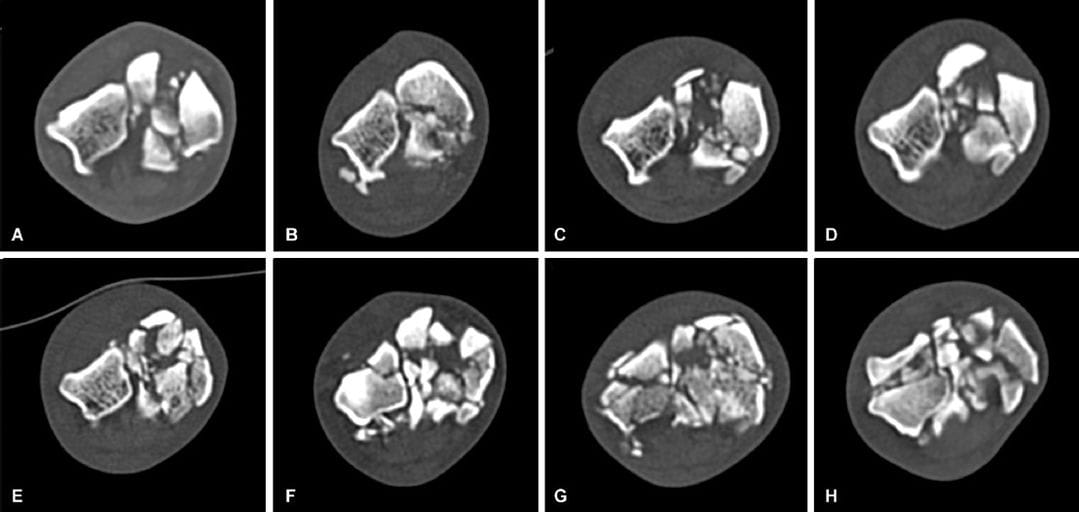

Transverse midbody sections of examples of the more moderately (A–D) and more severely (E–H) comminuted Type V fractures.

Central tarsal bone fractures are one of the most common major injuries in racing greyhounds, typically affecting the right hind limb due to high cyclic loading during counter-clockwise track racing. Historically, radiographs have been used to classify fractures into five main types, but radiography has limited sensitivity for detecting comminution. Computed tomography (CT) offers improved accuracy, but fracture type distribution has not been previously studied using CT in greyhounds.

-59 were Type V (severely comminuted)